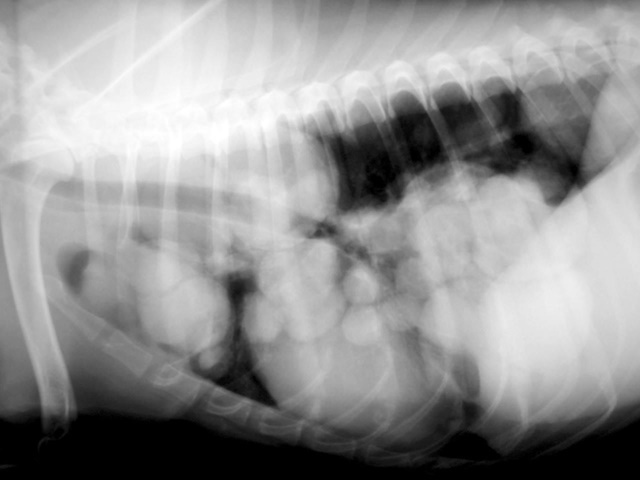

This dog had rapid shallow breathing. Radiographs of the lungs showed diffuse metastatic nodules in the lungs.